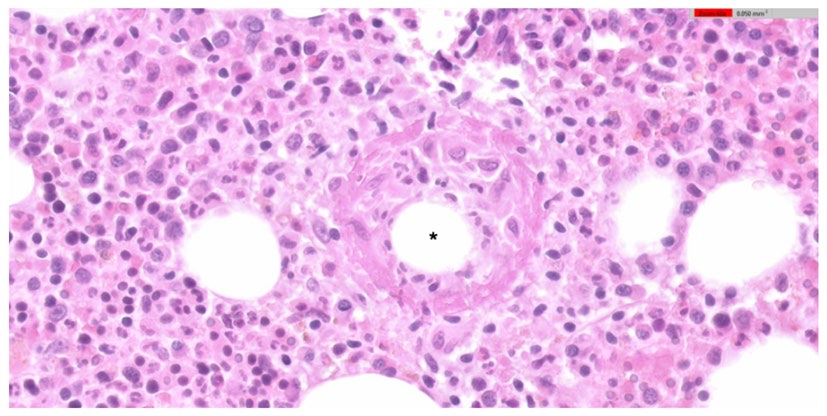

Images in Medicine